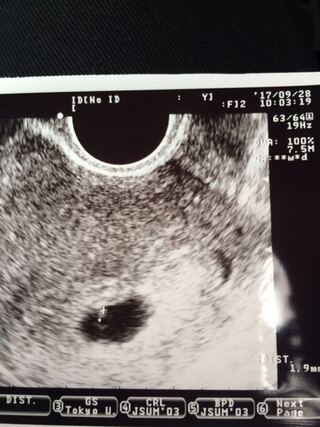

5週の胎嚢サイズ→10~25mm 6週の胎嚢サイズ→15~30mm 7週の胎嚢サイズ→~37mm 胎嚢サイズの目安については以上。 自分の実際の胎嚢サイズと 照らし合わせてみると、 ※経過が分かりやすいように 心拍確認できるまでの結果を 先に載せてしまいます。妊娠4週になると見えてくる、「胎嚢」「卵黄嚢」って何? 妊娠5週になると脳や神経、心臓など臓器、それに手足や目、耳の原型もできるってホント? 妊娠6~7週で、心臓の動き出す!? まだ「胎児」と呼んでもらえない妊娠2ヶ月の「胎芽」時代の赤ちゃんのこと、母体のこと。今までの治療のこと~心拍確認~ テーマ: 不妊治療 公式ハッシュタグランキング: エコー検査 16 位 今までの治療の続きです 19年11月頃のお話です 6週0日の診察で胎嚢が小さいことを指摘され、一週間後の診察日まではかなり

妊娠6週0日で胎嚢しか確認できない 初めて質問させて頂きます 不妊治療 Okwave

bt23 6週0日 胎嚢確認のためにクリニックへ 49歳からのハワイでの不妊治療